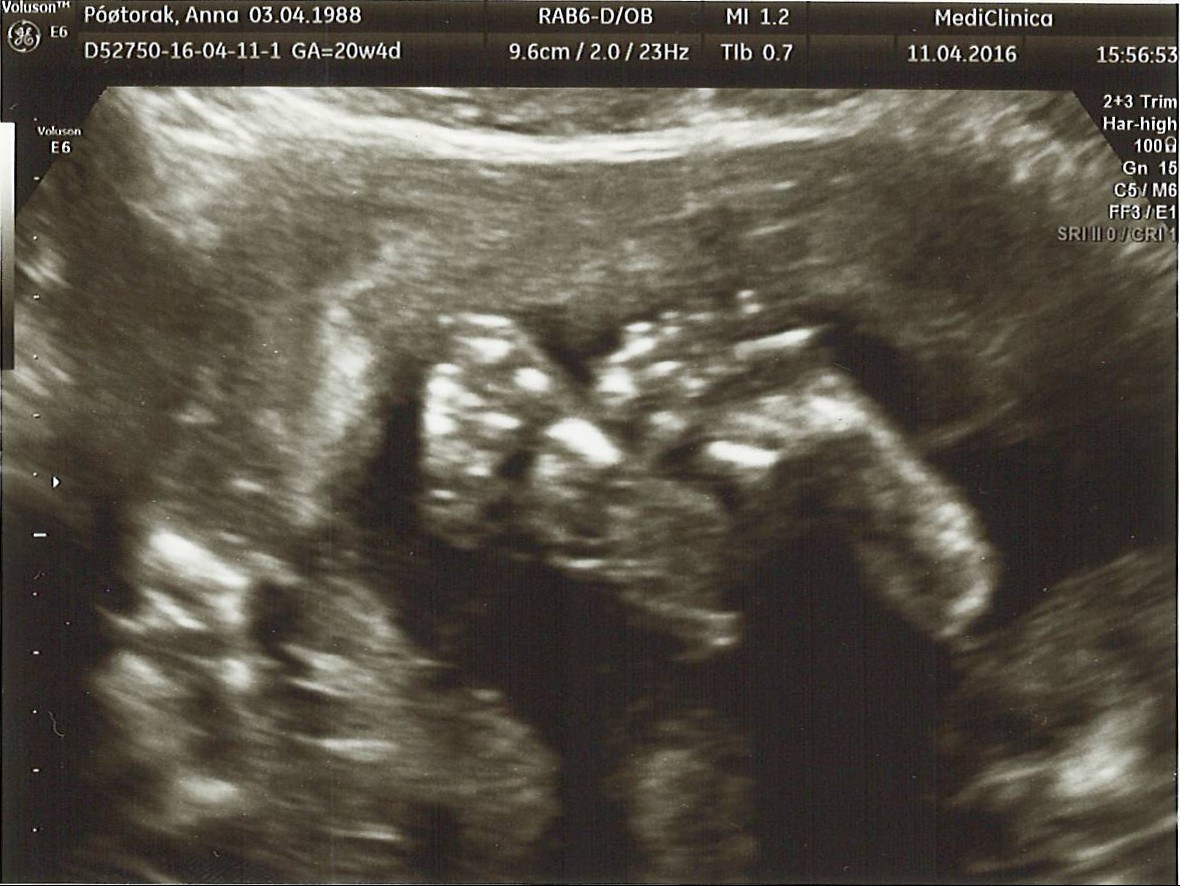

Ja też dziś miałam wizytę :) Jesteśmy w tym samym tygodniu i dniu ciąży i chłopaki ważą prawie tyle samo, mój 668 gram :)Niestety nam nie udało się strzelić takich ładnych portretów ;), ale fajnie było widać ja Mały łapie się za nóżki :)